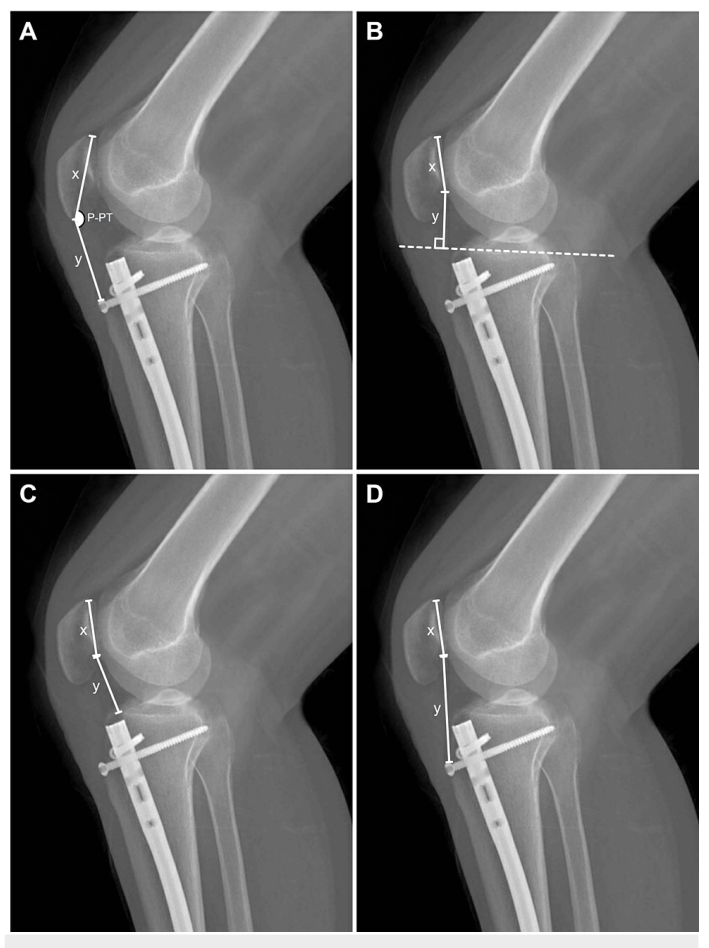

图1:胫骨轴骨折接受扩髓髓内钉治疗的患者的侧面直接射线照片上髌骨高度指数和矢状角的样本测量值:(a)Insall-Servati指数和髌骨-髌腱角,(B)Blackburne-Peel指数,(C)Caton-Deschamps指数,和(D)改良Insall-Slvati指数。

材料和方法:研究了2019年至2022年期间接受胫骨IMN并在术后随访中出现膝关节前侧疼痛的患者,与至少两个门诊临床对照,间隔至少一个月。在半屈曲患者的侧位直接x线片上测量髌骨高度指数(Insall-Salvati、blackburn - peel、Caton-Deschamps和改良Insall-Salvati)和矢状角度(髌骨-髌骨肌腱角度)。作为对照组,对同一患者的对侧完整肢体x线片进行测量。